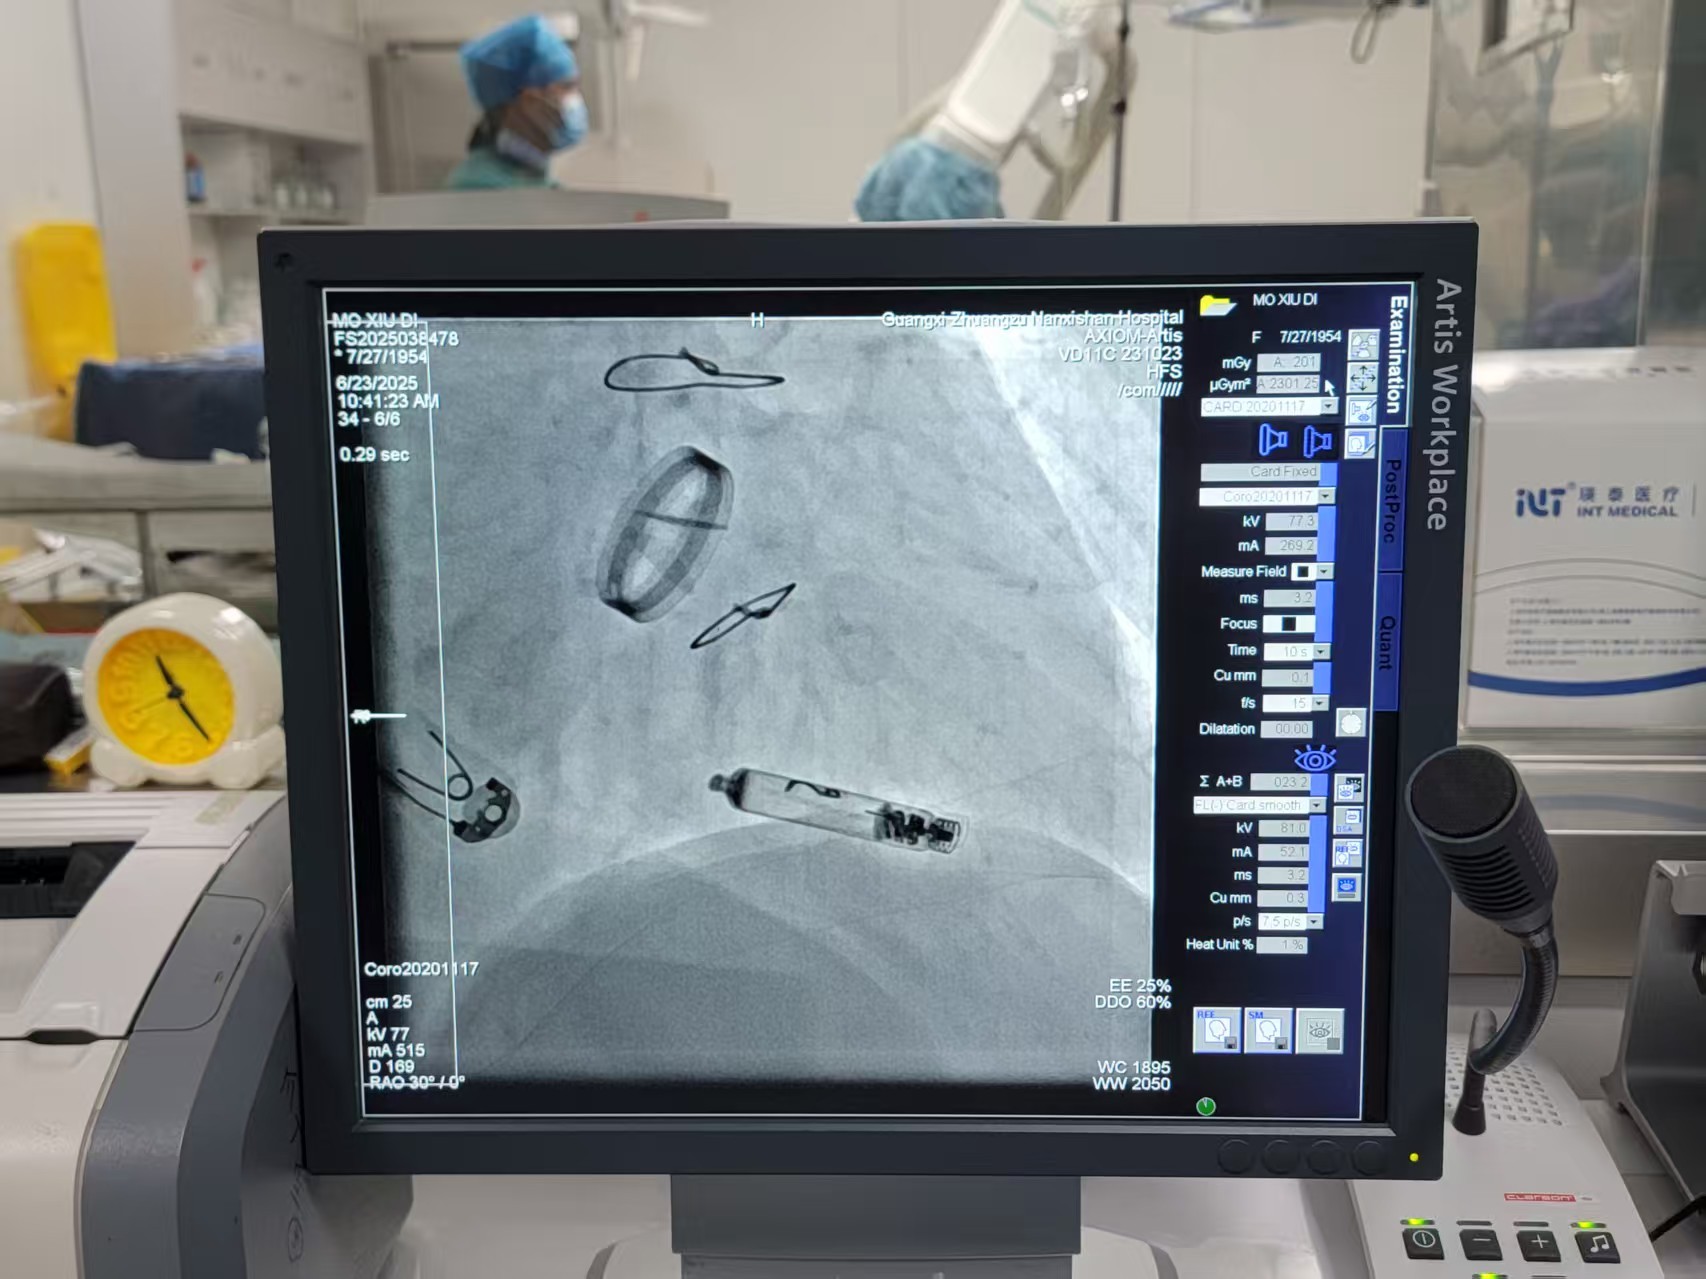

面对这一治疗难题,心血管内科一病区邓英松副主任医师团队决定采用前沿的雅培Aveir VR无导线起搏技术。该技术核心优势在于其微创性和安全性:起搏器仅重2.4克,形似胶囊,通过股静脉穿刺,经导管精准输送至右心室间隔部植入。

手术无需切开皮肤制作囊袋,也无需植入心内膜导线,从根本上规避了囊袋出血和感染风险。特别值得一提的是,该起搏器是全球唯一具备实时心内电信号标测技术的无导线起搏器,医生可在释放前精确定位最佳起搏点(莫女士手术中测得阈值0.5V@0.4ms),显著提升手术精准度和长期效果。此外,其独特的螺旋电极可主动旋入心肌固定,并具备未来可安全取出的设计。